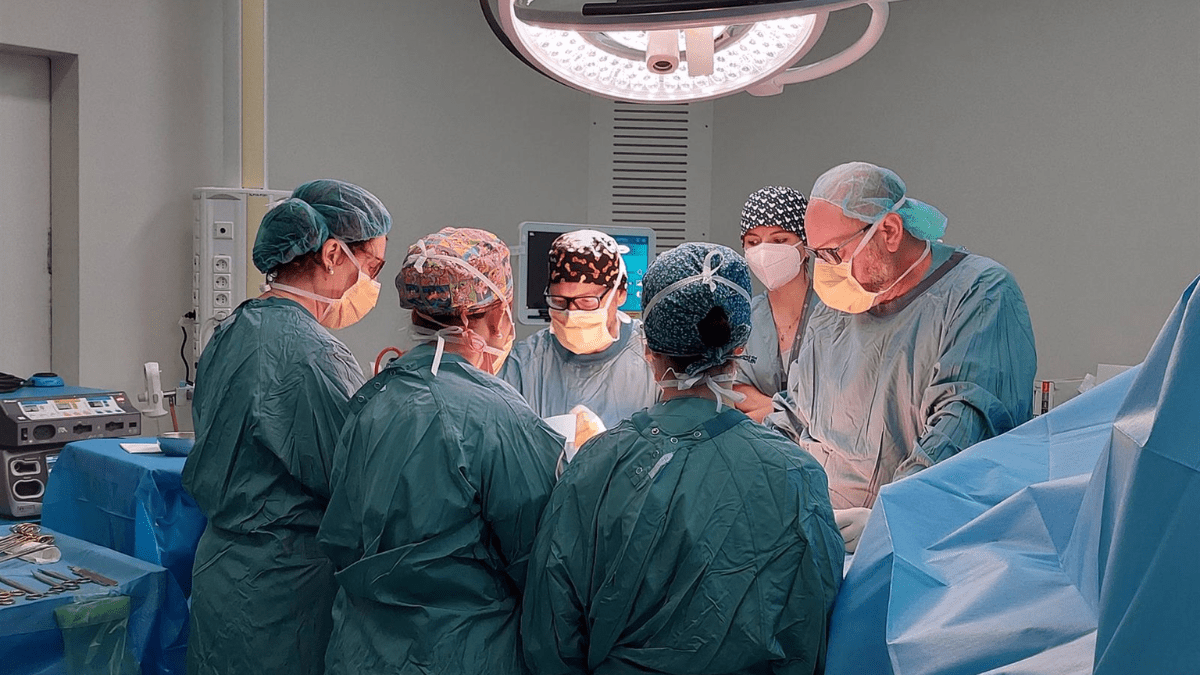

Para llevar a cabo la intervención, se requiere un equipo multidisciplinario compuesto por profesionales de diversos servicios

Para llevar a cabo esta intervención, se requiere un equipo multidisciplinario compuesto por profesionales de diversos servicios, como Cirugía Plástica, Cirugía General, Anestesiología y Enfermería. La operación se aborda en tres fases, y según Fernández-Garrido, el éxito depende de la planificación quirúrgica.